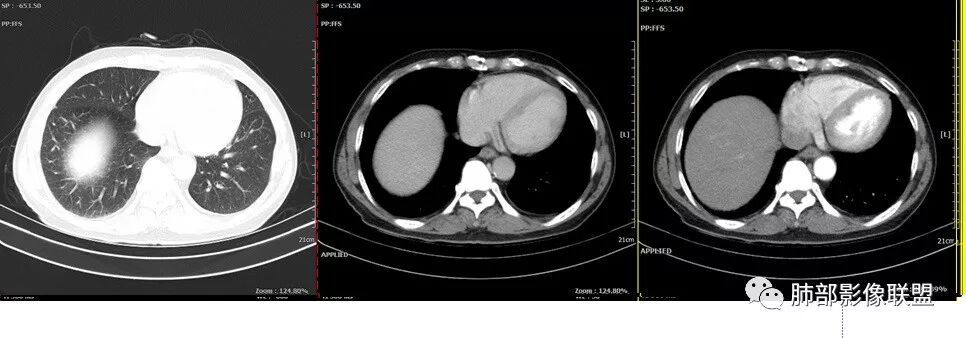

雪上一枝蒿(陈显静):

复查的HRCT

初学者:

这个什么治疗后的。当时应该抗炎后先复查一下就知道了。

化疗2次。

Coke with ice:

这次的间质性改变考虑什么?癌淋还是?

应该是阻塞性肺炎,抗感染后查PET CT的时候左上肺已经有部分吸收了。